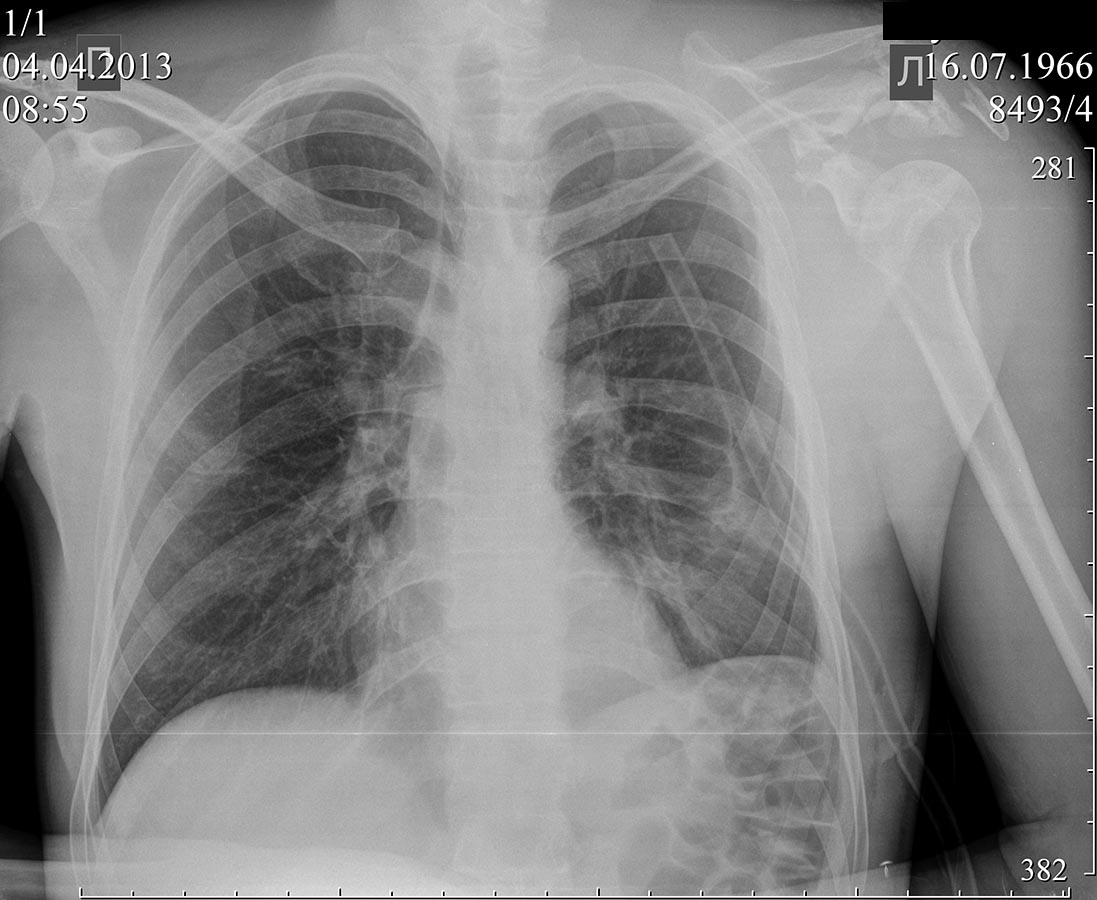

Пациент 46 лет, травма на производстве 30.03.13.упала металлическая балка на левый плечевой сустав.

Диагноз: сочетанная травма, оскольчатые переломы лопатки и акромиального конца левой ключицы, перелом шейки левой плечевой кости,перелом 2-5 ребер слева с повреждением легкого, пневмоторакс. По поступлению торакоцентез слева, косыночная иммобилизация левого плечевого сустава. В настоящее время легкое расправилось, торакальный дренаж удален. Уважаемые коллеги, помогите, пожалуйста, определиться с объемом оперативного вмешательства на плечевом суставе.

Так еще и вывих грудинного конца правой ключицы, а слева не перелом акромиального конца ключицы, а перелом акромиона лопатки, шейки лопатки

Ну, хотелось бы не на снимок легких смотреть, а на плечевой сустав. В идеале в трех проекциях и КТ